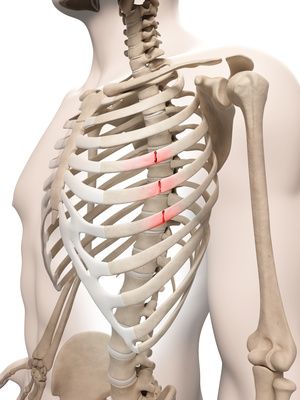

DOI: 10.7759/cureus.60157 여기서 주목한 점은 해당 선수가 SLAP 병변 외에도 어깨 관절의 '가동 범위 제한'이 심했다는 겁니다. 우리가 어깨 관절을 검사할 때 쓰는 두 가지 테스트에서 양성으로 나왔는데요. 1. 결합 외전 검사(CAT, Combined Abduction Test): 견갑골을 고정한 뒤 팔을 위로 올려(Flexion) 가동 범위가 줄어드는지 보는 검사 2. 수평 굴곡 검사(HFT, Horizontal Flexion Test): 어깨를 몸통 쪽으로 수평하게 모을 때 가동 범위가 줄어드는지 보는 검사  B,D 그림처럼 해당 검사에서 양성이라는 건, 어깨 관절의 아랫쪽과 뒷쪽이 꽉 조여져 있다는 것을 의미합니다. 정상적으로 팔을 들 때에는 어깨뼈와 팔뼈가 미끄러지듯이 움직여야 하는데, 관절이 꽉 조여 있으면이 중심축이 자꾸 틀어지게 됩니다. 이렇게 되면 팔을 올릴 때마다 SLAP 병변 위치에더 큰 압력이 가해지고,증상이 계속해서 악화되었던 것이죠. > 신경의 유착이 > > 어깨를 꽉 잡고 있다! 그렇다면 어깨 움직임을 제한하는 ‘꽉 조이는 느낌’은 어디에서 오는 걸까요? 연구진은 CAT와 HFT 검사 시 가장 심하게 늘어나는 신경을 주목했습니다. ◆ CAT (어깨 올림) 검사 시: 어깨 관절 아래쪽에 위치한 흉배신경 (Thoracodorsal Nerve, TDN)이 가장 늘어나고요. 광배근(Latissimus Dorsi) 등의 중요한 근육을 지배합니다. ◆ HFT (수평 모으기) 검사 시: 어깨 관절 뒤쪽에 위치한 액와신경 (Axillary Nerve, AxN)이 가장 늘어나고, 소원근(Teres Minor)과 같은 근육을 지배합니다. 이 사례에서는 이 두가지 신경 주변 조직이염증으로 인해 유착되면서어깨의 가동 범위를 제한하고, 결과적으로 SLAP 병변의 통증을 유발했다고 가설을 세웠습니다. 즉, 구조적인 문제가 아니라 신경 포착 증후군이 통증의 원인일 수 있다는 새로운 관점이죠. > 관절경 수술이 아닌 > > 비수술 치료 그래서 선택한 치료법이 바로 ‘하이드로다이섹션(Nerve Hydrodissection)’, 즉 신경 박리술입니다.

B,D 그림처럼 해당 검사에서 양성이라는 건, 어깨 관절의 아랫쪽과 뒷쪽이 꽉 조여져 있다는 것을 의미합니다. 정상적으로 팔을 들 때에는 어깨뼈와 팔뼈가 미끄러지듯이 움직여야 하는데, 관절이 꽉 조여 있으면이 중심축이 자꾸 틀어지게 됩니다. 이렇게 되면 팔을 올릴 때마다 SLAP 병변 위치에더 큰 압력이 가해지고,증상이 계속해서 악화되었던 것이죠. > 신경의 유착이 > > 어깨를 꽉 잡고 있다! 그렇다면 어깨 움직임을 제한하는 ‘꽉 조이는 느낌’은 어디에서 오는 걸까요? 연구진은 CAT와 HFT 검사 시 가장 심하게 늘어나는 신경을 주목했습니다. ◆ CAT (어깨 올림) 검사 시: 어깨 관절 아래쪽에 위치한 흉배신경 (Thoracodorsal Nerve, TDN)이 가장 늘어나고요. 광배근(Latissimus Dorsi) 등의 중요한 근육을 지배합니다. ◆ HFT (수평 모으기) 검사 시: 어깨 관절 뒤쪽에 위치한 액와신경 (Axillary Nerve, AxN)이 가장 늘어나고, 소원근(Teres Minor)과 같은 근육을 지배합니다. 이 사례에서는 이 두가지 신경 주변 조직이염증으로 인해 유착되면서어깨의 가동 범위를 제한하고, 결과적으로 SLAP 병변의 통증을 유발했다고 가설을 세웠습니다. 즉, 구조적인 문제가 아니라 신경 포착 증후군이 통증의 원인일 수 있다는 새로운 관점이죠. > 관절경 수술이 아닌 > > 비수술 치료 그래서 선택한 치료법이 바로 ‘하이드로다이섹션(Nerve Hydrodissection)’, 즉 신경 박리술입니다.  DOI: 10.7759/cureus.60157 1. 흉배신경 (TDN) 치료: 환자는 눕거나 엎드린 자세에서 진행됩니다. 광배근(LD), 대원근(TM), 견갑하근(SSC) 사이를 지나는 흉배동맥을 이정표(landmark) 삼아 신경 다발을 찾아냅니다. 이곳에 약침을 정밀하게 주입하여, 신경과 주변 유착된 조직 사이를 부드럽게 분리시키고요.